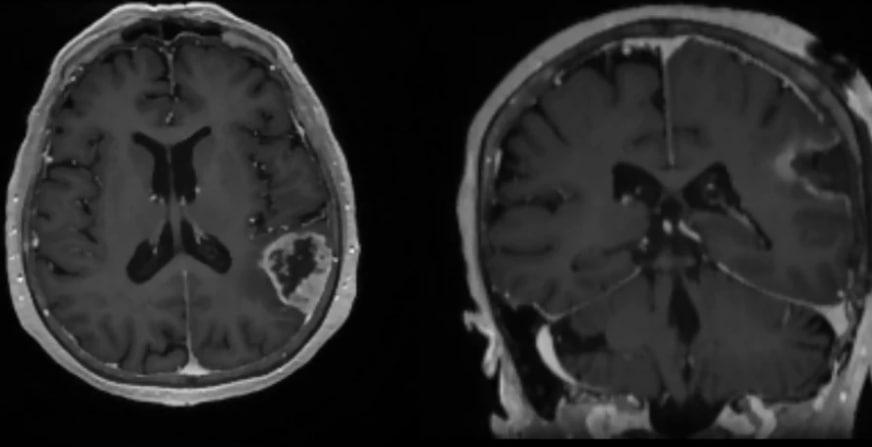

После курса лечения состояние улучшилось: пенсионерка вернулась к домашним делам, готовила, убирала. Но вскоре начала заикаться. Обследования, включая МСКТ и МРТ, выявили объёмное образование в левой теменной доле. Опухоль размером 3×4×5 сантиметров оказалась причиной ухудшения самочувствия.

Сначала женщина сомневалась, стоит ли ложиться под нож, но всё же решилась на операцию. В феврале 2026 года её прооперировали в НИИТО. Новообразование удалили полностью под нейронавигационным контролем и отправили на гистологию.